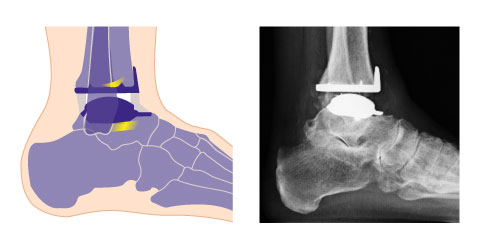

Die Sprunggelenksprothese wird zementfrei befestigt

Die Sprunggelenksprothese (OSG-TEP) wird nach genauer Anpassung durch Probeimplantate und Kontrolle der Lage zementfrei eingesetzt. Der Spezialist verklemmt die Originalkomponenten der Prothese am Knochen. Durch die sorgfältige Präparation der knöchernen Struktur können sich die Implantate nicht mehr verschieben.

Die Sprungbeinkomponente wird primär durch beschichtete Führungsbolzen am Knochen fixiert, sogenannte Press-Fit-Zapfen. Die Scheinbeinkomponente überzieht die Knochenfläche der Tibia. Die Rückseite hat je nach Prothesentyp kleine Dorne für die knöcherne Fixierung.

Beide Komponenten des Sprunggelenkersatzes sind auf der am Knochen anliegenden Seite mit einer speziellen Hydroxylapatit-Beschichtung überzogen und mit Titan bestrahlt, um ein sicheres Einwachsen des Knochens zu erreichen.

Die dritte Komponente der individualisierten 3-Komponenten-Sprunggelenksprothese ist ein frei beweglicher Kunststoffgleitkern aus Polyethylen, der die Bewegung zwischen den beiden Gelenkpartnern vermittelt. Der Gleitkern hat eine quaderförmige Form.

Mögliche Fehlstellungen erkennt der Arzt bei der klinischen Untersuchung sowie durch die Podometrie und die orthopädische Ganganalyse. Durch bildgebende Verfahren wie die digitale Volumentomographie (DVT) und Röntgenaufnahmen unter Belastung des Sprunggelenks (im Stehen) lassen sich die genaue Position und die Stellung der knöchernen Komponenten analysieren. Festigkeit und Beweglichkeit des Sprunggelenks werden im Rahmen der klinischen Untersuchung geprüft.